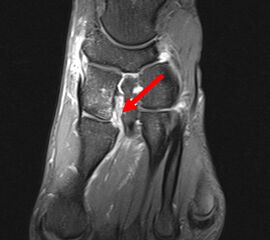

Das Lisfranc-Ligament selbst lässt sich am Besten im MRT beurteilen. Gelegentlich lässt sich im MRT ein Knochenmarksödem als einziges Zeichen einer nicht dislozierten Fraktur finden. Die MRT-Diagnostik ist allerdings eher unklaren interossären Erweiterungen bei persistierenden Schmerzen zur Suche nach isolierten Bandverletzungen vorbehalten 7511.

Zum Lesen der Bildbeschreibung und zur Vollansicht bitte das Bild anklicken.